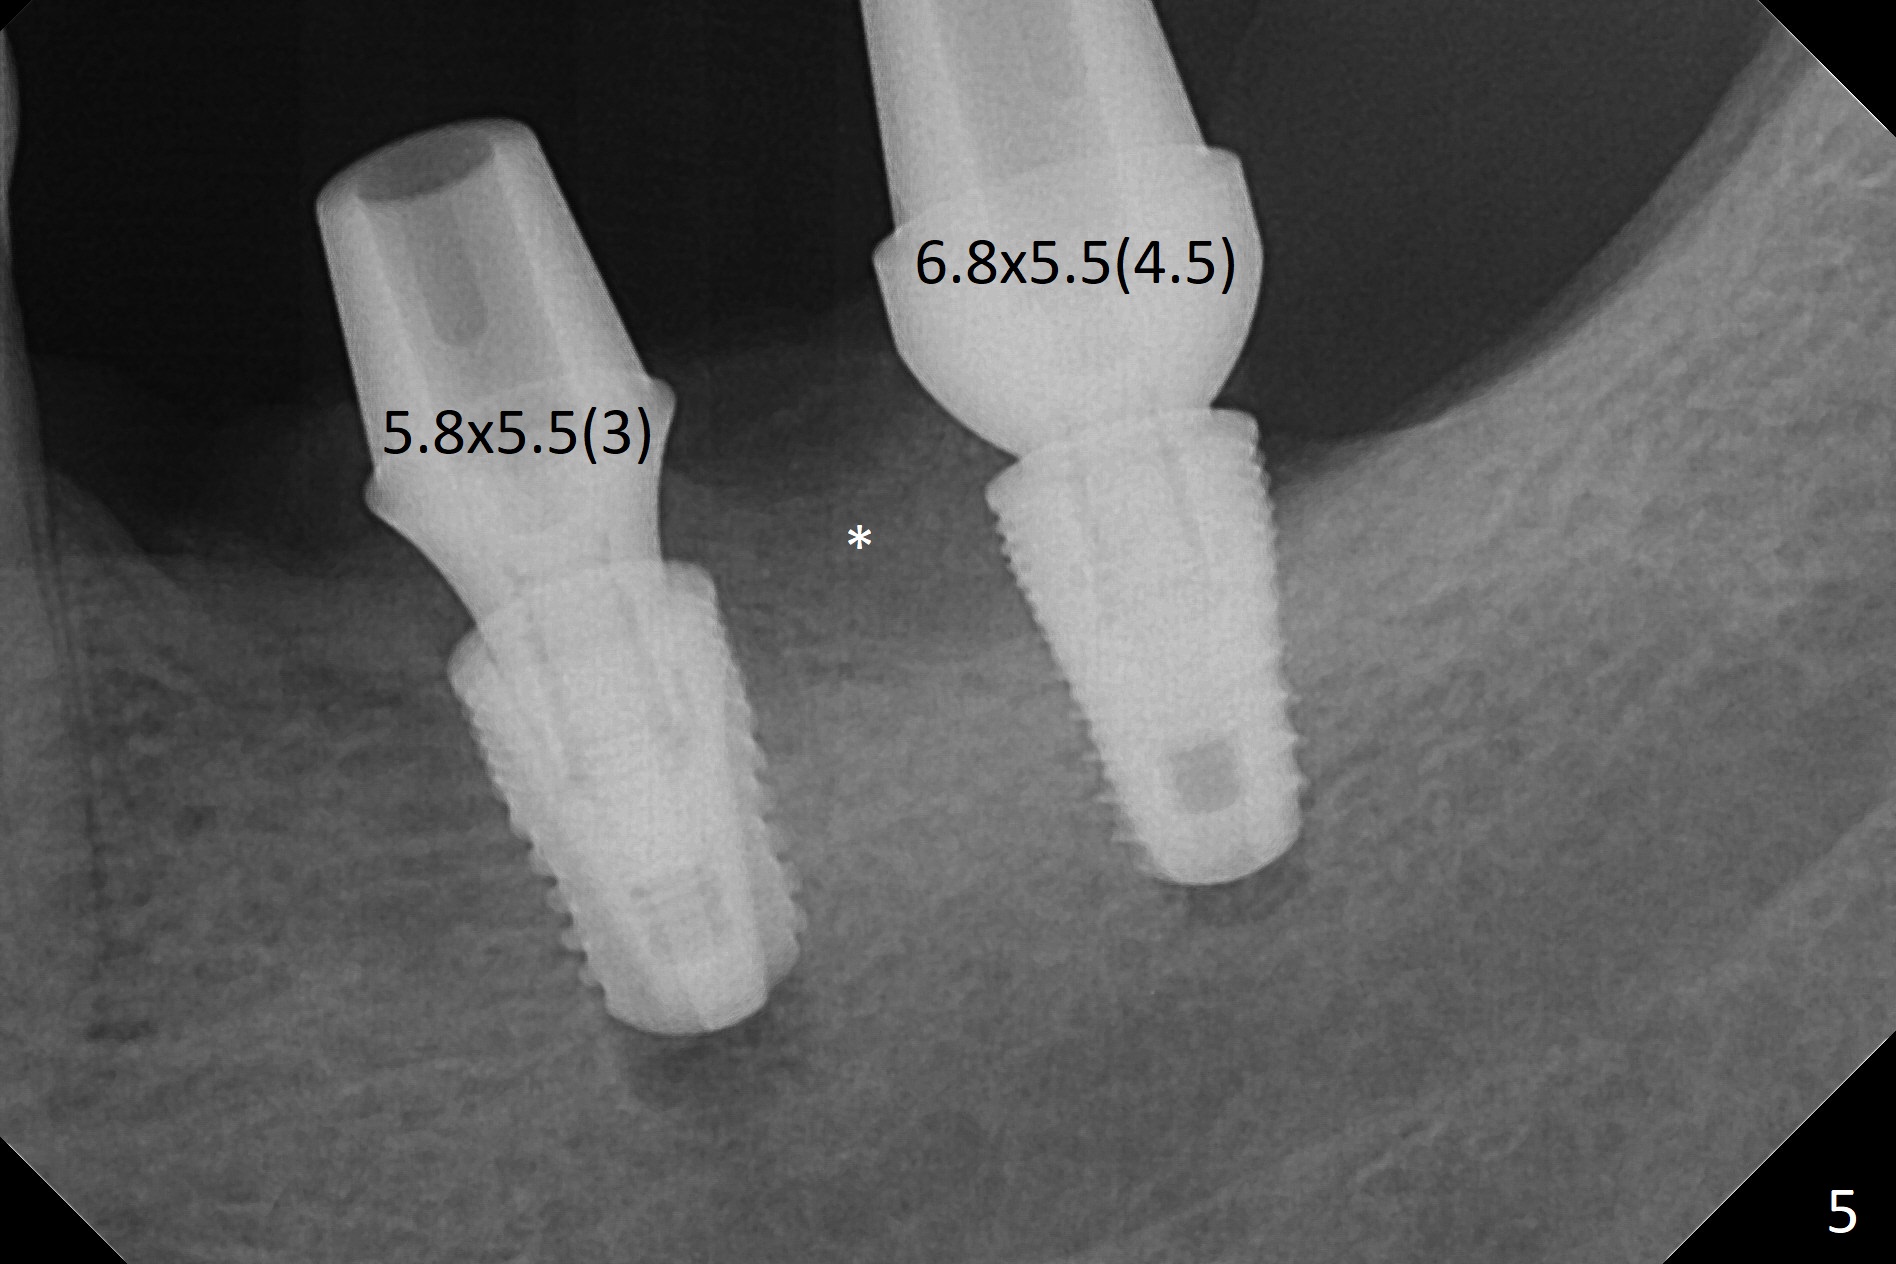

Preop photo shows severe mesial tilt of the tooth #18 (Fig.1). After extraction, the osteotomy is established in the apical end of the socket, where the buccolingual width is limited. It appears that an extra wide implant (5.9 mm) may perforate one of buccolingual plates. On the other hand, the buccal plate (Fig.2 double arrows) is intact and approximately 2 mm tall, whereas the lingual one is thin and lower. Initial osteotomy confirms that bone heights at #18 and 19 are 6 and 8 mm, respectively. Counting 2 mm of the buccal plate and bone graft lingually, a 8 mm long implant may be a practical option at the site of #18. After initial placement of two of 5x8 mm SM implants (Fig.3), the depth of the implant at #19 is adjusted twice (Fig.4,5). With placement of autogenous and allograft (Vanilla, Fig.5 *)) and abutments, a piece of cotton pellet is placed in each abutment well (access, Fig.6 *). Periodontal dressing is applied to the abutment wells for additional retention (Fig.7 *). Due to local poor oral hygiene, splinted provisional is fabricated 4 months postop (Fig.8) in preparation for limited orthodontic uprighting the tooth #20. The patient has pain with mastication at #18 eleven months post cementation (Fig.9). It appears that both of the implants should be removed with immediate replacement and bone graft. Prepare 4 PRF and sticky bone. The new implant will be 5.0 or 5.5x5 mm (Fig.10 green) with 2.3 mm platform (white). A block graft will be harvested from the ipsilateral ramus using 9/8 and 6/5 mm trephine burs for 2-3 mm in depth (Fig.11 blue). The ring graft will be seated around the platform over the implant (Fig.12).